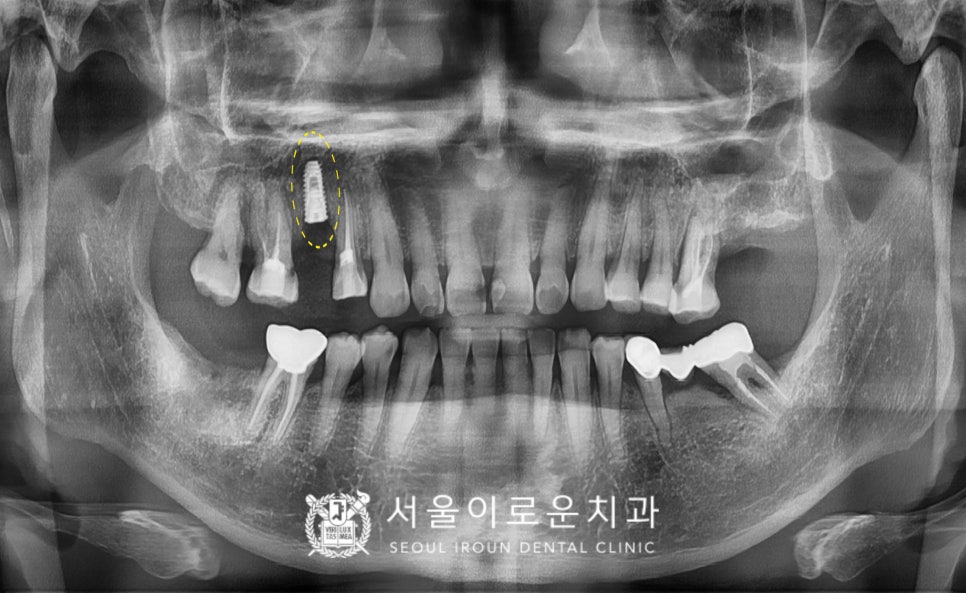

오른쪽 위턱 두 번째 작은 어금니(#15)는

발치 후 염증조직을 깨끗하게 제거하고

소독한 후에 뼈이식을 동반한

임플란트 즉시 식립을 도와드렸는데요.

발치 후 즉시 식립을 하게 되면

잇몸 조직의 손상과 출혈, 붓기도 적어

통.증도 감소되며 무엇보다

치료 기간이 단축되는 장점이 있답니다.

그리고 오른쪽 위턱 첫 번째

작은 어금니(#14)도

뿌리 끝까지 깔끔하게

신경치료를 마무리해 드렸습니다.

또한 오른쪽 위턱 첫 번째 큰 어금니(#16)와

앞니(#11,12) 모두

충치를 말끔하게 제거한 뒤

레진으로 보강하여

크라운 치료를 도와드렸습니다.

임플란트와 크라운 보철 치료가

마무리 된 사진입니다.